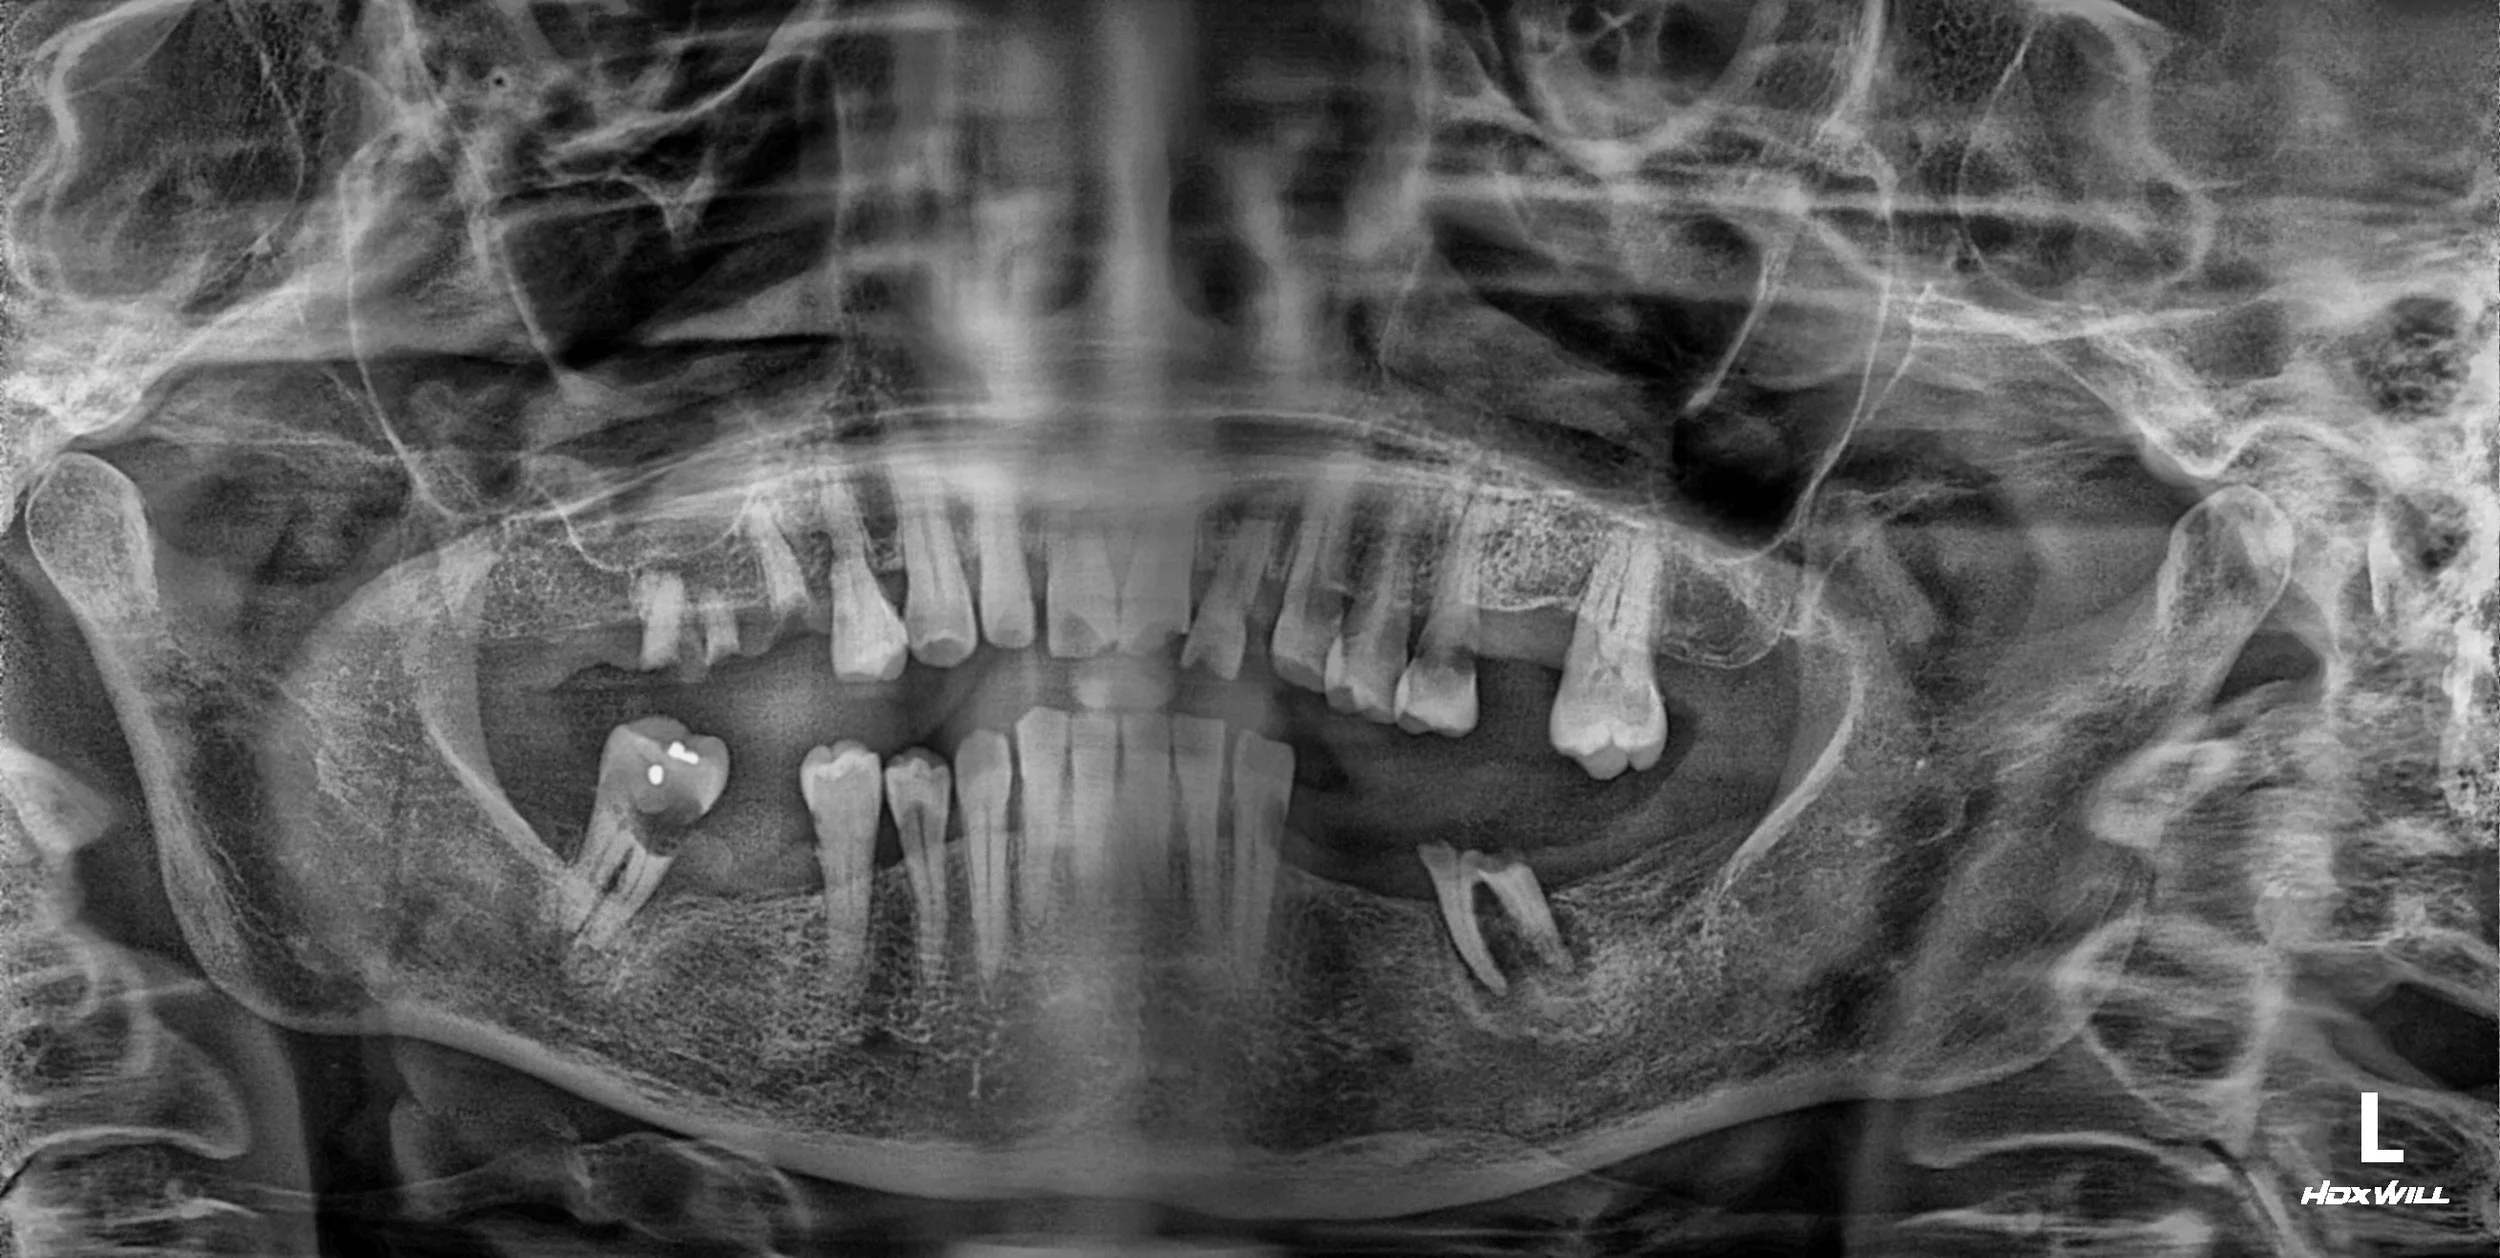

38. Comprehensive Full-Arch Reconstruction: Reversing the Domino Effect of Tooth Loss

Management of Generalized Severe Periodontitis and Posterior Bite Collapse in a Female Patient in her 60s. A Systematic Approach to VDO Recovery and Strategic Esthetic Rejuvenation.

37. Reclaiming Functional Comfort: Correcting Iatrogenic Occlusal Failure

Resolution of Incomplete Mouth Closure and TMJ Instability in a Female Patient in her 60s. A Conservative but Definitive Approach through Selective Occlusal Adjustment and Posterior Implant Support.